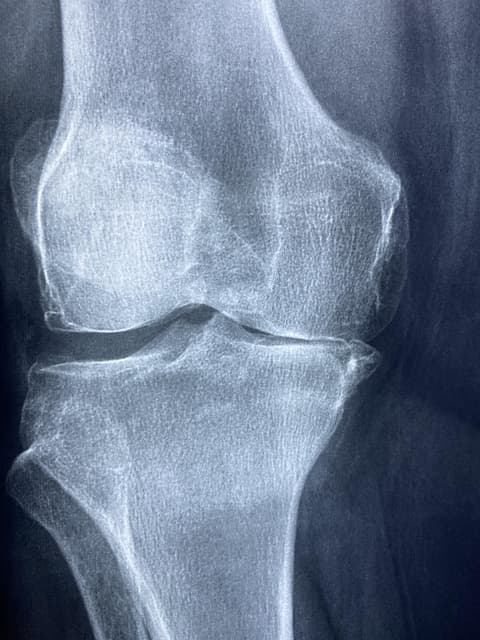

1. 퇴행성 관절염(골관절염)

- 가장 흔한 관절염으로, 나이가 들면서 관절 연골이 점차 닳아 없어지면서 발생합니다.

- 주로 무릎, 엉덩이, 손가락, 척추 등 몸무게가 많이 실리는 관절에서 잘 생깁니다

- 무릎: 걷거나 계단을 오를 때 통증이 심해지고, 심하면 관절이 휘거나 물이 차기도 합니다.